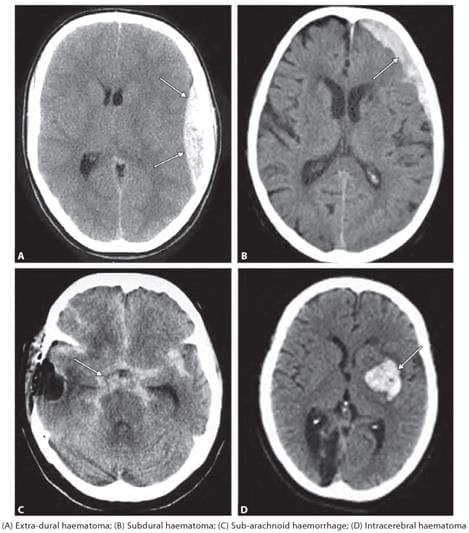

A 55-year-old patient presented with headache and confusion. There is a history of fall one week back. He also has personal history of chronic alcoholism. NCCT findings as shown below, point towards: (NEET-PG 2023)

Detailed Solution for Test: Anatomy - 3 - Question 7

The medical history of an older patient (experiencing brain atrophy) with chronic alcoholism, who does not present immediately in emergency, suggests a potential case of subdural haematoma (bleeding of bridging veins).

• The NCCT findings should display a concavo-convex shape, with the bleeding not limited by the suture lines.

Extradural haematoma: Symptoms typically manifest immediately (within minutes to hours; not weeks), accompanied by a rapid decline in consciousness due to it being an arterial bleed that leads to a swift increase in intracranial pressure.

• The NCCT reveals a hyperdense (whitish) biconvex bleeding pattern that does not cross the suture lines.

Subarachnoid haemorrhage: This may arise from the rupture of an aneurysm (for instance, a berry or saccular aneurysm), presenting acutely and rapidly, often described as ‘the worst headache of my life’, along with a related finding of blood in a lumbar puncture.

• The CT scan indicates signs of acute (hyperdense/whitish) bleeding in the subarachnoid cisterns or ventricles.

Intracerebral haemorrhage: These bleeds might result from systemic hypertension, leading to the rupture of Charcot-Bouchard microaneurysms, typically found in the lenticulostriate branches that supply the basal ganglia (putamen, globus pallidus).